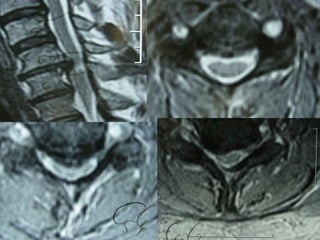

66 wf LBP urosepsis(E Coli blood and urine) claustrophobia

Occult Fracture